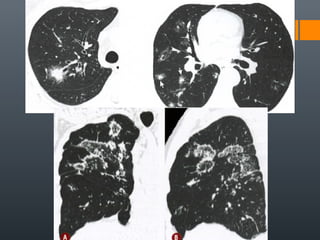

O documento discute vários conceitos radiológicos incluindo consolidação, atelectasia, nódulos, pseudocavidades e padrões intersticiais, fornecendo definições, sinais e diagnósticos diferenciais para cada tópico. Ele também discute a redução da atenuação pulmonar e fornece um link para mais informações.